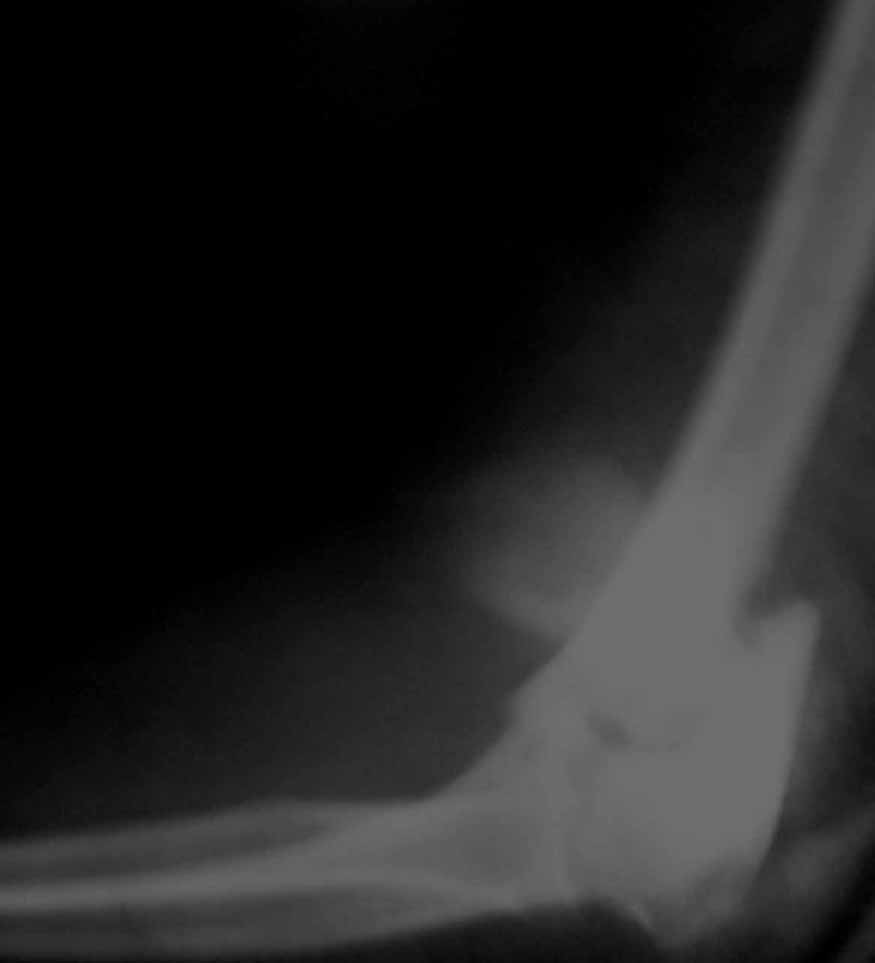

Уважаемые коллеги! Мужчина, 28 лет. 1 сутки назад получил бытовую травму - закрытый чрезмыщелковый перелом правой плечевой кости со смещением. По месту жительства в ЦРБ - репозиция, иммобилизация. Направлен к нам.

Место болезни без особенностей, неврологических и сосудистых расстройств нет. Принято решение об оперативном лечении - чрескостный остеосинтез.Предложения по конструкции АВФ (т.к. мнения расходятся)? Заранее благодарю! С уважением,А.В.ВладзимирскийДонецкий НИИ травматологии и ортопедииДонецк, Украина